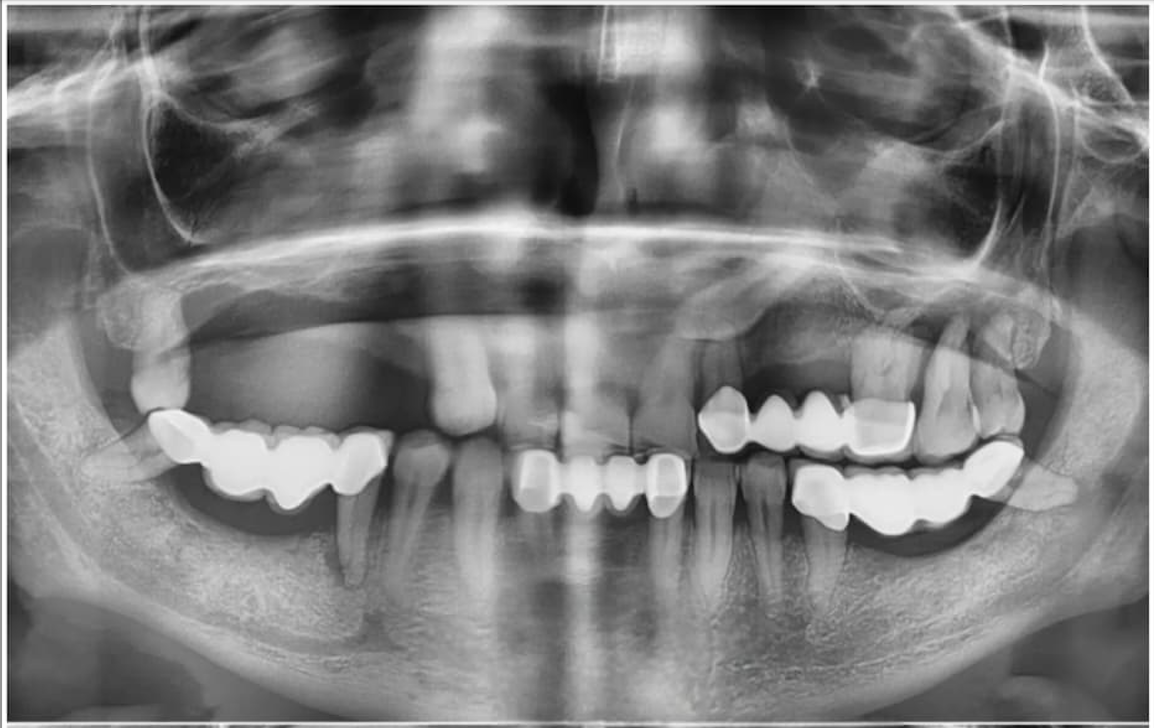

Zygomatic Implants Case Study

Case Study

Advanced Zygomatic

Implant Rehabilitation

Fixed prosthetic rehabilitation with zygomatic implants for a patient presenting with extreme bone deficiency and failed previous implant attempts from another facility.

In this complex case where traditional implant treatments were technically impossible to apply, the ZAGA Concept allowed us to provide a stable, long-term solution through specialized zygomatic surgery, restoring both function and aesthetics.

• Removal of failed implants from external centers

• Severe bone loss management via Zygomatic Concept

• Full functional and aesthetic fixed restoration